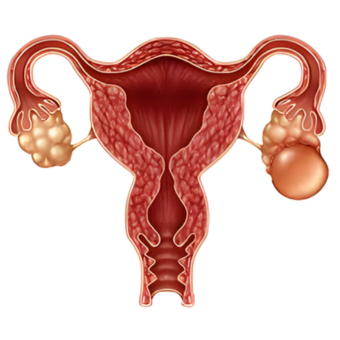

Ovarian Cysts

Endometriosis